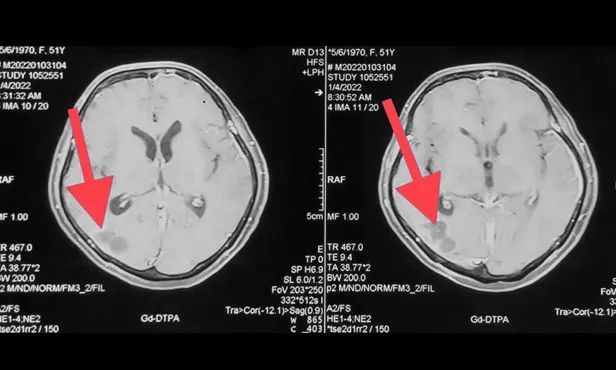

▲ 刚入院时病灶影像

▲ 完成穿刺,黑色囊液被顺利引流